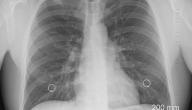

أورام حميدة في الرئة

ينتج ورم الرئة الحميد عن معدلات غير طبيعية لانقسام الخلايا، أو موت الخلية في أنسجة الرئة أو في الشّعب الهوائية التي تؤدي إلى الرئتين، وقد يتشكّل الورم أو تراكم الأنسجة غير الطبيعي عندما تنقسم الخلايا بسرعة كبيرة أو لا تموت كما ينبغي في الوضع الطّبيعي، وفي حال كان الورم بقطر 3 سنتيمترات أو أقلّ؛ فإنّه يُعرَف باسم العقيدات، وتُسمّى هذه العقيدات العقيدات الرئوية عندما تتشكّل في الرئتين.[١]

أمّا الكتلة التي قطرها أكبر من 3 سنتيمتر فإنها تُسمّى الورم، وثُعدّ أورام الرئة الحميدة غير سرطانية، لذلك لا تنتشر إلى أجزاء أخرى من الجسم، كما أنها تنمو ببطء، أو قد تتوقف عن النمو أو تنكمش في بعض الحالات، وهي عادةً لا تشكّل خطرًا على حياة الفرد، ولا تحتاج إلى استئصالها.[١]

لا تظهر أية أعراض على الشخص المُصاب بأورام حميدة في الرئة، إذ يكتشف حوالي 90% من الأشخاص وجود أورام حميدة لديهم في الرئة عن طريق الصدفة عندما يُخضَعون لتصوير الأشعة السينية أو الأشعة المقطعية لسبب آخر. وتوجد بعض الحالات الأخرى التي تظهر عليها بعض الأعراض؛ مثل ما يأتي:[١]